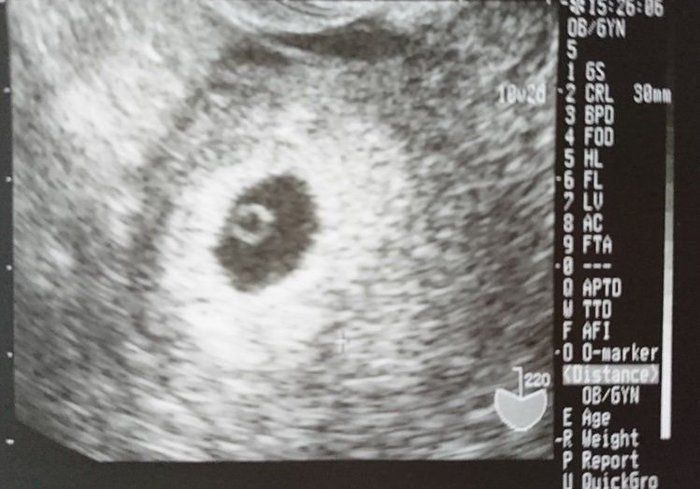

ちゃじゅびさんの妊娠6週目のエコー写真 胎芽が見える

胎嚢が大きくなり、そのなかに胎芽(7週未満の赤ちゃん)が確認できるようになりました。